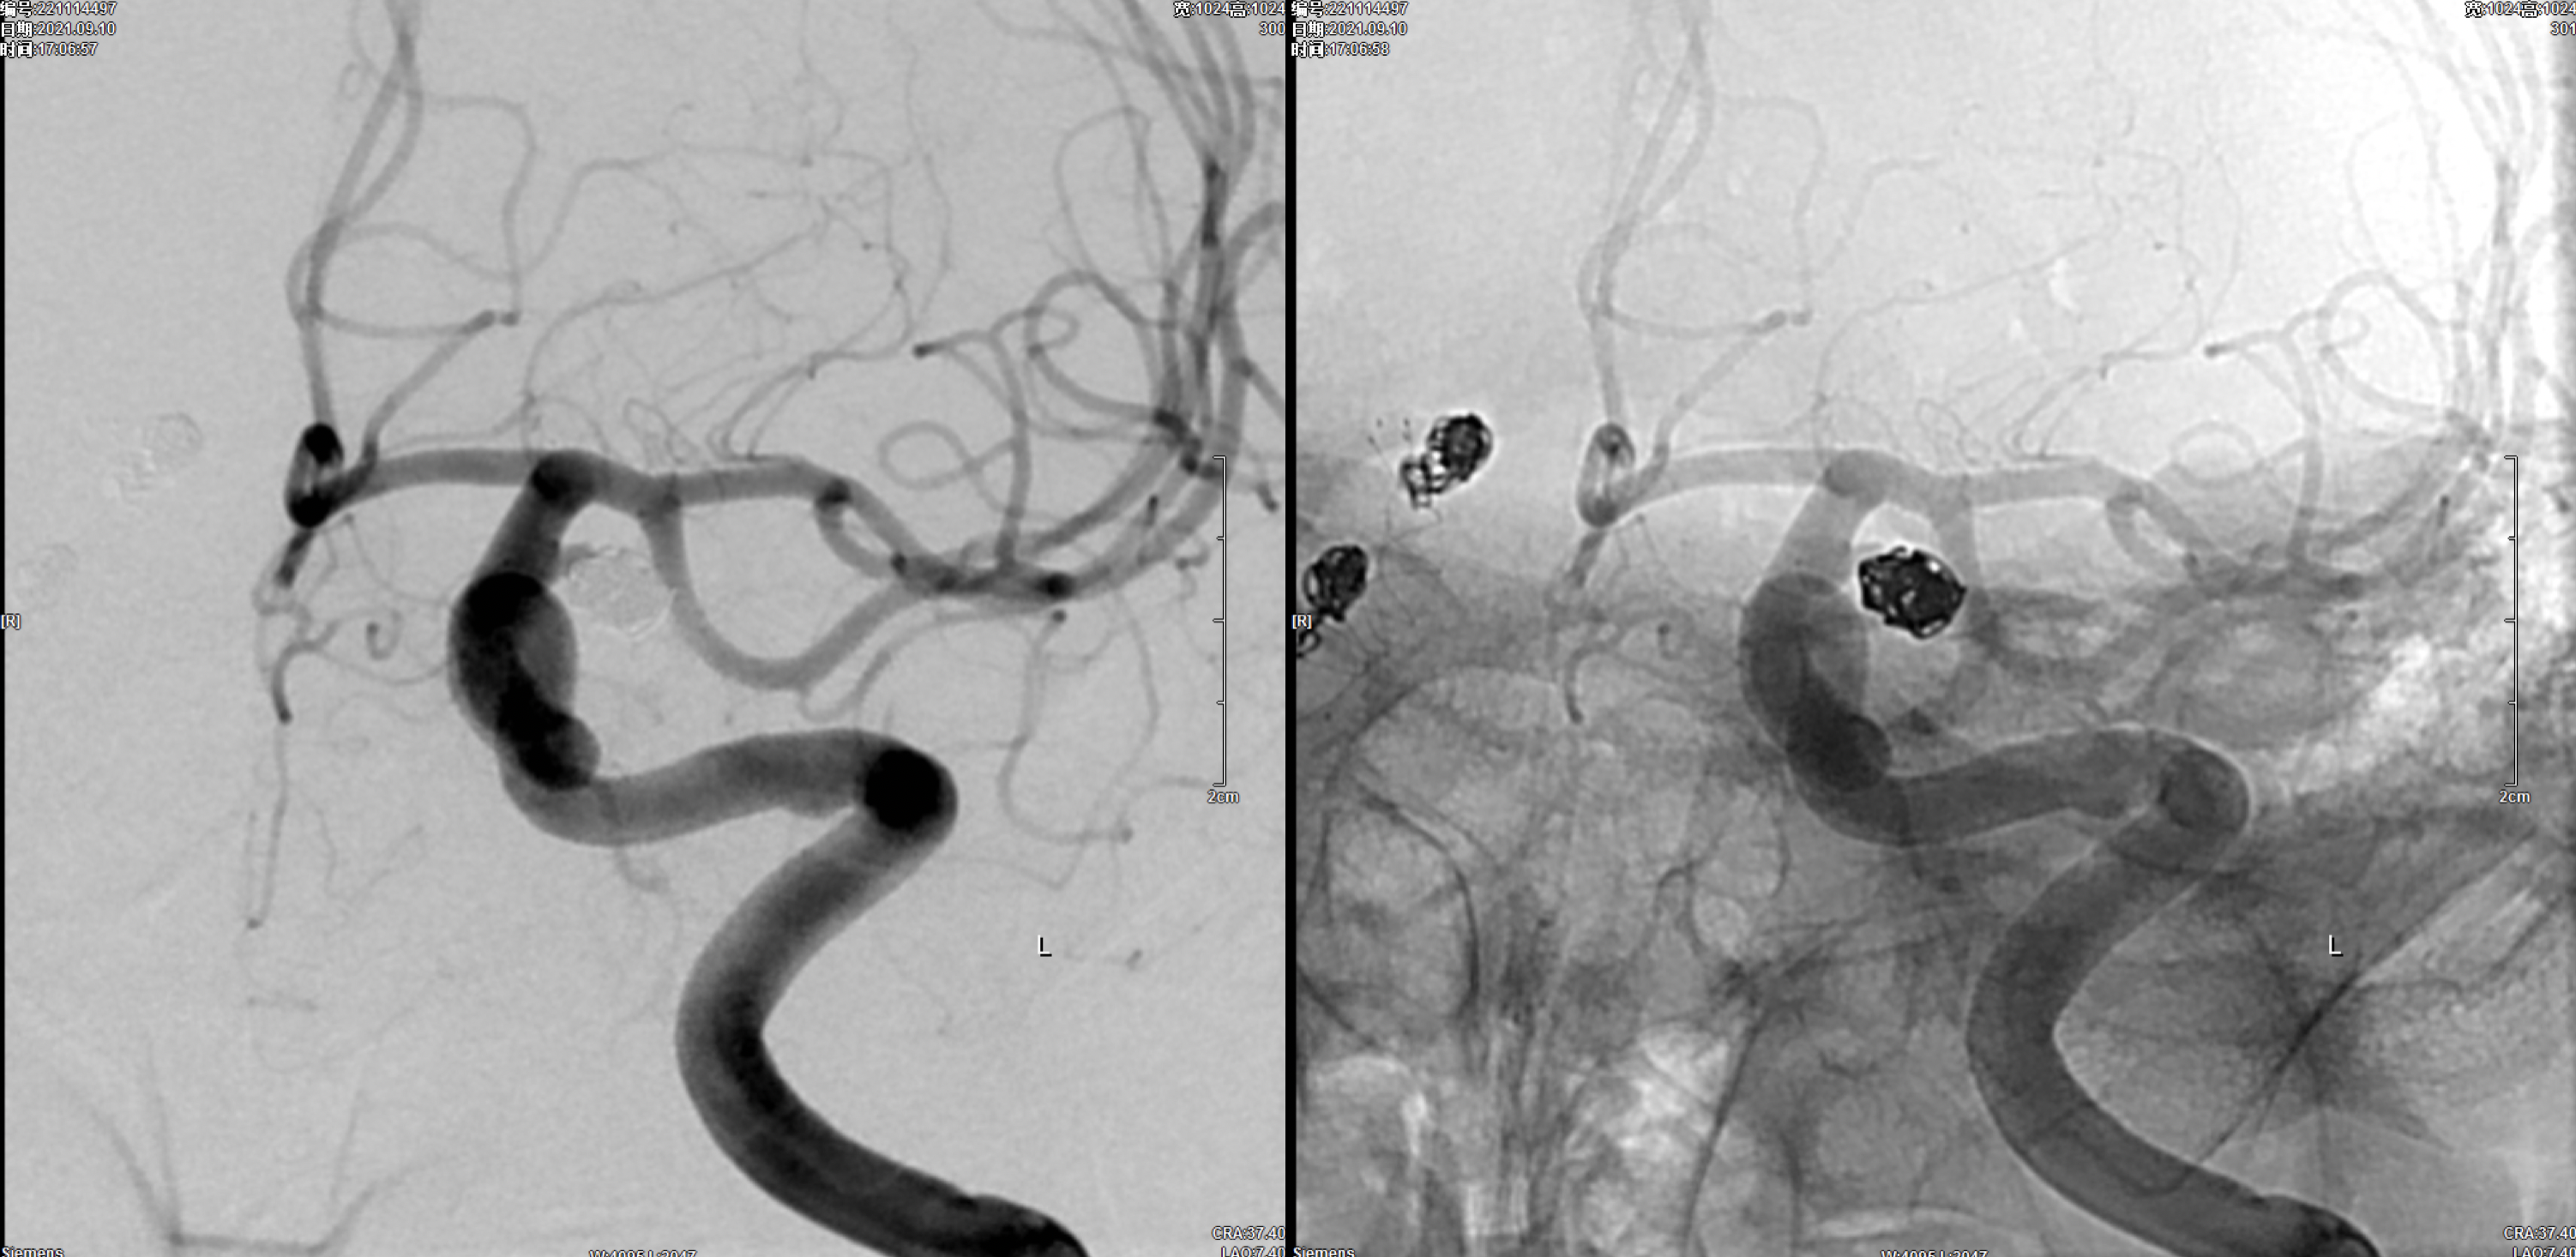

7F长鞘+6F Navien建立左侧颈内动脉栓塞通路后,栓塞微导管超选进入动脉瘤瘤腔内。

行单纯栓塞,工作位造影及蒙片显示:动脉瘤栓塞完全!撤除栓塞导管。

术后左侧颈内动脉正侧位造影显示:动脉瘤栓塞完全!各级血管通畅。撤除通路系统。